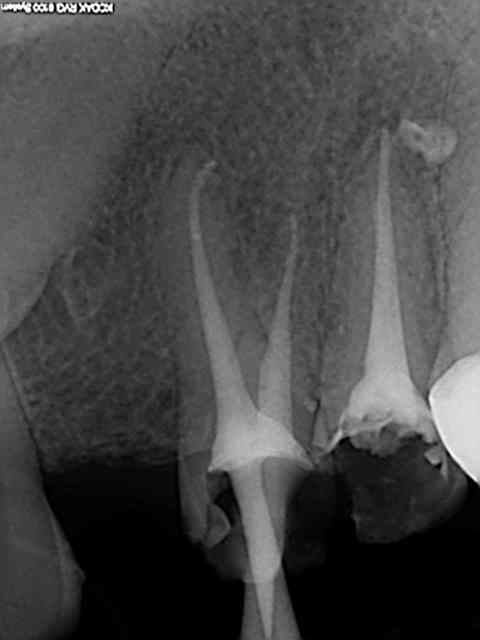

Monocone = minimum syndical vu le tarifs opposables de merde, je ne m'en cache pas, mais plus de lentulo. Des fois obturation au système B ou au mac spaden.

Apex défoncés, je ne comprend pas expliques. C'est vrai qu'il est plus simple de faire des endos à 4 mm de l'apex comme je vois souvent pour éviter de le leser je suppose.

Loin de moi l'idée de faire les meilleures endo du monde mais par contre je suis assez satisfait du résultat immédiat et à long terme, vu le minimum de temps passé à les faire (10 mn par canal en moyenne)

Tiens les endos de la semaine, que d'apex défoncés !-))

La 47 en fin le distal est obturé au système B (bouchon apical) et au mac spaden pour la partie coronaire, tu vois la différence à la radio ? Alors l'apex défoncé il faut avoir l'oeil ! peut etre mais à 25 centièmes et à conicité 6 %........-))